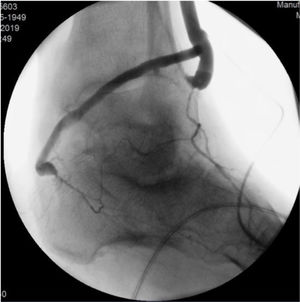

La fase siguiente de la planificación es la angiografía convencional diagnóstica, que realizamos sistemáticamente, excepto en pacientes con enfermedad renal crónica avanzada (depuración de creatinina <30ml/min). La inyección de contraste (80cc, 6ml/s, 600PSI de presión), se realiza mediante una punción femoral retrógrada con introductor 4F. Esta técnica permite el reclutamiento de todos los colaterales responsables de la irrigación de la pierna y del pie, desde la arteria femoral profunda, obteniendo así un gran detalle anatómico (fig. 2).

La calidad de la angiografía es crucial para la planificación de cualquier revascularización distal o ultradistal, con imágenes en 2 proyecciones y tiempos de exposición prolongados que permitan visualizar las arterias del pie. Los tiempos de exposición pueden alcanzar los 60s y, como tal, nos parece esencial la realización/supervisión de este examen por parte de un miembro del equipo con experiencia en este tipo de revascularización, con el fin de optimizar el uso de la radiación y disminuir la cantidad de contraste. En pacientes con contraindicación para la angiografía, se realiza la planificación basada exclusivamente en los hallazgos del eco-Doppler.